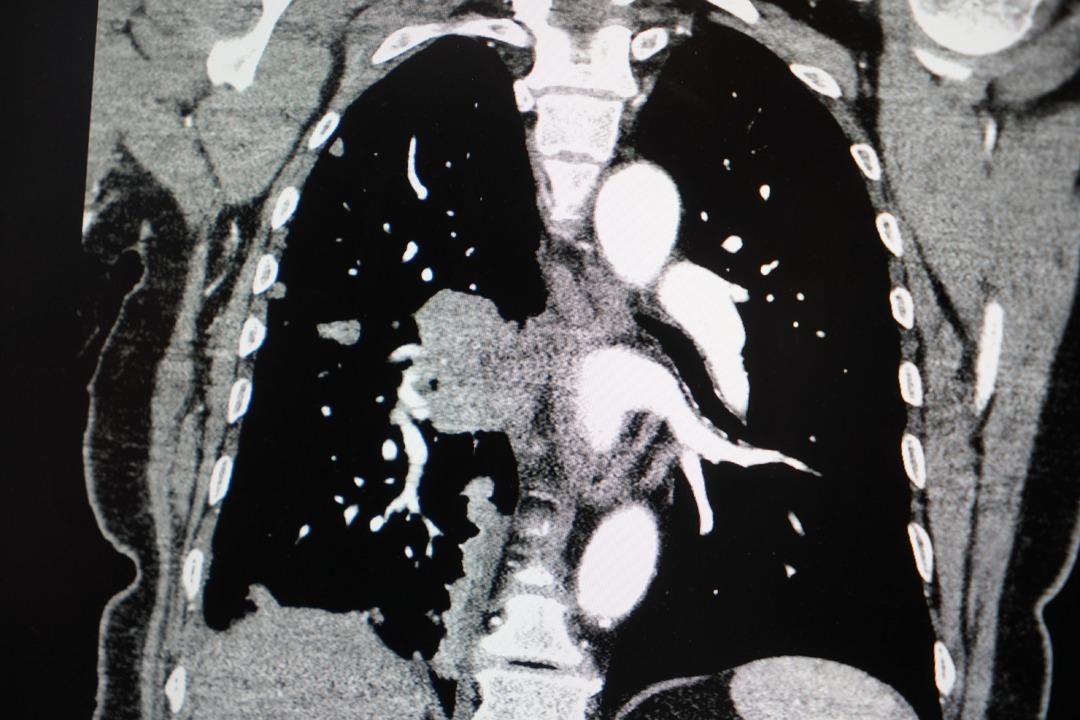

Akciğer kanseri vakalarındaki artışa da dikkat çeken Özkaya, "Son yıllarda hem sigara içen hem de hiç sigara kullanmamış bireylerde akciğer kanseri vakalarında dikkat çekici bir artış görüyoruz. Özellikle kadınlarda adenokarsinom tipi akciğer kanseri belirgin şekilde artış göstermektedir., Yapılan son araştırmalara göre akciğer kanseri teşhislerinin yaklaşık yüzde 20'si hiç sigara içmemiş bireylerde konuluyor. Bunun en önemli nedeni pasif içiciliktir. Yani siz sigara içmeseniz bile, yakın çevrenizde sigara içiliyorsa akciğer kanseri riskiyle karşı karşıya kalabilirsiniz" ifadelerini kullandı.